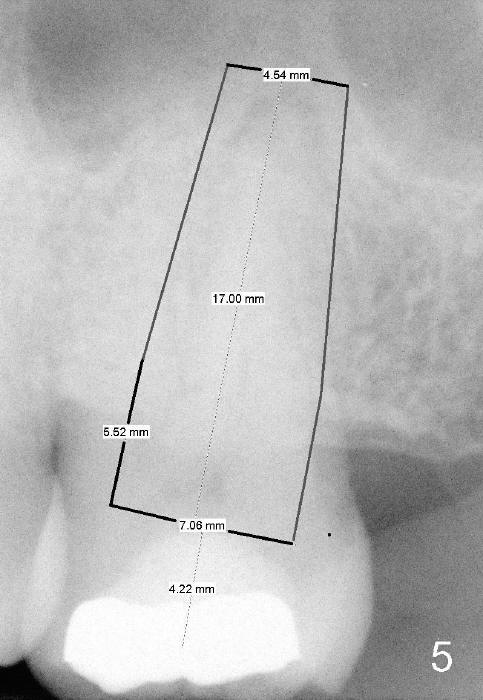

A 52-year-old black man fails to return to finish root canal therapy for the tooth #15; ultimately it is non-salvageable (Fig.1-3).  The tooth has 3 basically fused roots (Fig.4 black (buccal) and red (palatal) outlines), above which is the sinus septum (*).  By inserting an immediate implant into the sinus septum, primary stability should be high (Fig.5 vs. 6).